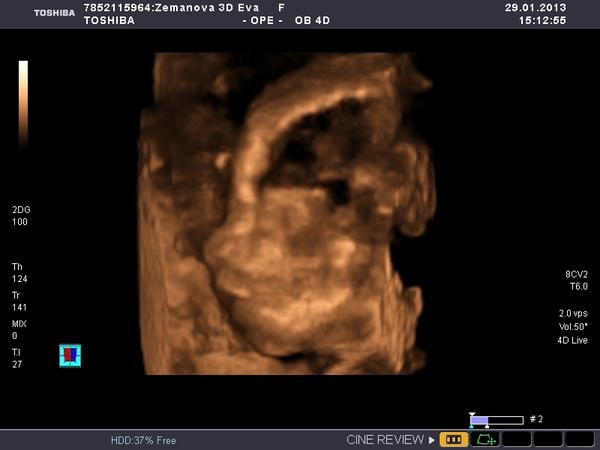

Ráno v 7:30 jsem opustila teplo svého domova a odjela sednout si k počítači a pracovat. Dosedla jsem v 8:10 a do teď u toho počítače dřepim (pár přestávek jsem měla, abych nekecala) a odhaduju, že ještě tak 2 hodiny tu dřepět budu a ráno v osm už mám zase vyzvedávat klienta a jet někam do horoucích pekel. A PAK MI NĚKDO VYSVĚTLETE, JAK TO NAŠI MYSLELI, KDYŽ ŘÍKALI,AŤ SE UČÍM, ABYCH MĚLA HEZKOU PRÁCI A MOHLA SI UŽÍVAT!?! jediný co mě s tím smiřuje, že můj hodný muž přijel a pomáhá mi, abychom to měli rychleji a má "prolhaná" matka je ve vedlejší kanceláři a dělá taky... Jestli se ve čtvrtek ukáže, že čekáme děvčátko, tak ho vychovám, aby se dobře vdalo a může být klidně úplně blbá.... 😀